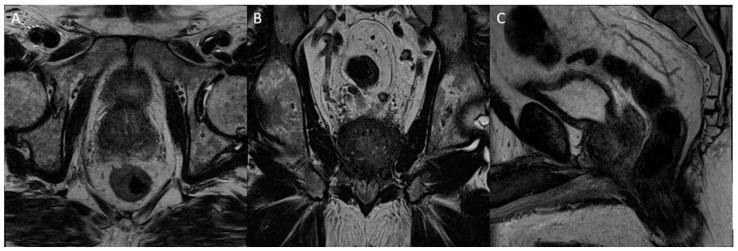

Tissue changes and the enlargement of the prostate, whether benign or malignant, are among the most common groups of diseases that affect men and can have significant impacts on length and quality of life. The prevalence of benign prostatic hyperplasia (BPH) increases significantly with age and affects nearly all men as they grow older. Other than skin cancers, prostate cancer is the most common cancer among men in the United States. Imaging is an essential component in the diagnosis and management of these conditions. Multiple modalities are available for prostate imaging, including several novel imaging modalities that have changed the landscape of prostate imaging in recent years. This review will cover the data relating to commonly used standard-of-care prostate imaging modalities, advances in newer technologies, and newer standards that impact prostate gland imaging.

组织变化以及前列腺肿大,无论良性还是恶性,都是影响男性的最常见疾病类别,会对生活长度和质量产生重大影响。良性前列腺增生(BPH)的患病率随年龄显著增加,几乎所有男性随着年龄增长都会受到影响。除皮肤癌外,前列腺癌是美国男性中最常见的癌症。影像学是这些疾病诊断和管理的重要组成部分。有多种前列腺成像方式可供选择,包括近年来改变了前列腺成像格局的几种新型成像方式。本综述将涵盖与常用的标准护理前列腺成像方式、新技术进展以及影响前列腺成像的新标准相关的数据。